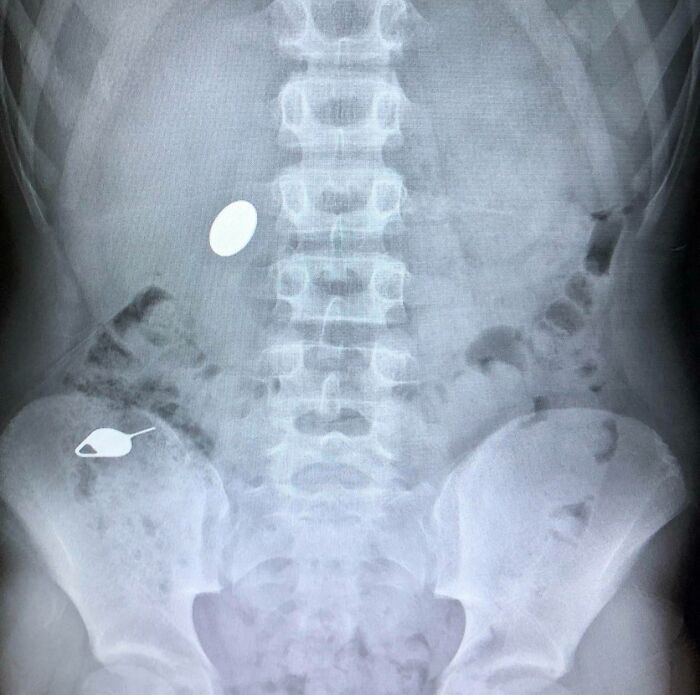

Moje dieťa zhltlo mincu, keď ukazovalo svojmu malému bratovi, ako deň predtým omylom zhltlo ihlu na otváranie slotu na SIM karty

Videl som to vo filmoch, ale ani vo sne by ma nenapadlo, že to uvidím v reálnom živote